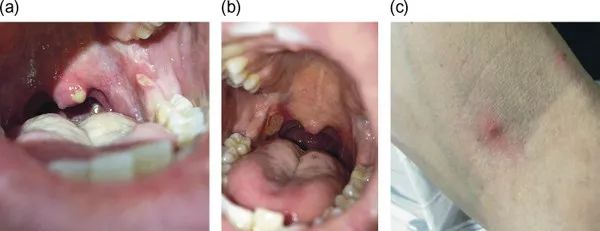

临床病史和检查发现复发性口腔溃疡(图1a和b)并持续长达数周,溃疡位于会厌及左侧会厌皱襞处(图2)和直肠黏膜另见溃疡灶。两个病变的活检均显示非特异性炎性浸润,以中性粒细胞为主。该患者还报告了丘疹性皮肤病变和针刺反应阳性(图1C)。

图1(a和b)覆盖在悬雍垂、后磨牙三角区和软腭上有大量疼痛性口腔溃疡。(c)丘疹性皮损,针刺反应阳性。